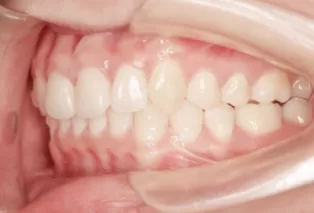

Photos intra-orales